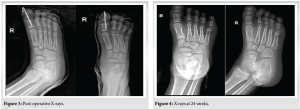

A 7-year-old healthy, fully vaccinated boy was brought by his parents to our institution’s pediatric ED complaining of right big toe deformity and open wound after a history of trauma while playing with his sibling at home, described as tripping on a hyper-plantarflexed big toe. (Fig. 1 and 2).

The patient was initially attended and examined by an emergency physician who then started intravenous (IV) cefazolin and consulted orthopedic surgery as a case of open first interphalangeal joint dislocation. Upon examination from the orthopedic resident oncall, the patient was found to have an approximately 3 cm transverse laceration along the plantar and lateral aspect of the base of the right big toe. After irrigation with normal saline, no visible contamination was noted, and the articular surface of the proximal phalanx was exposed. Cap refill noted to be <2 s and gross toe sensation was intact. Radiographs confirmed a medial HIJ dislocation. The nature of condition and management plan was discussed with the patient and his parents, and consents were obtained. After obtaining narcotic analgesia, closed reduction was successfully done by the orthopedic resident oncall, utilizing a traction and lateral translation maneuver, the wound was covered by wet-to-dry sterile gauze and immobilized with plaster and buddy taping. The patient was then booked for exploration, irrigation, and debridement with K-wire fixation as CAT-II. The patient underwent surgical intervention under general anesthesia the next day, found to have an intact FHL tendon and volar plate, the capsule was repaired, wound was irrigated thoroughly, and the HIP joint was fixed with a retrograde 1.8 mm Kirschner wire, wound closed primarily with prolene. Proper K-wire placement and joint reduction confirmed under orthogonal intra-operative radiographs utilizing C-arm. Cap refill was noted to be <2 s. The joint was immobilized with a short backslab with extension to toes, reflected distally to cover the bent K-wire tip to avoid inadvertent removal by the child (Fig. 3).